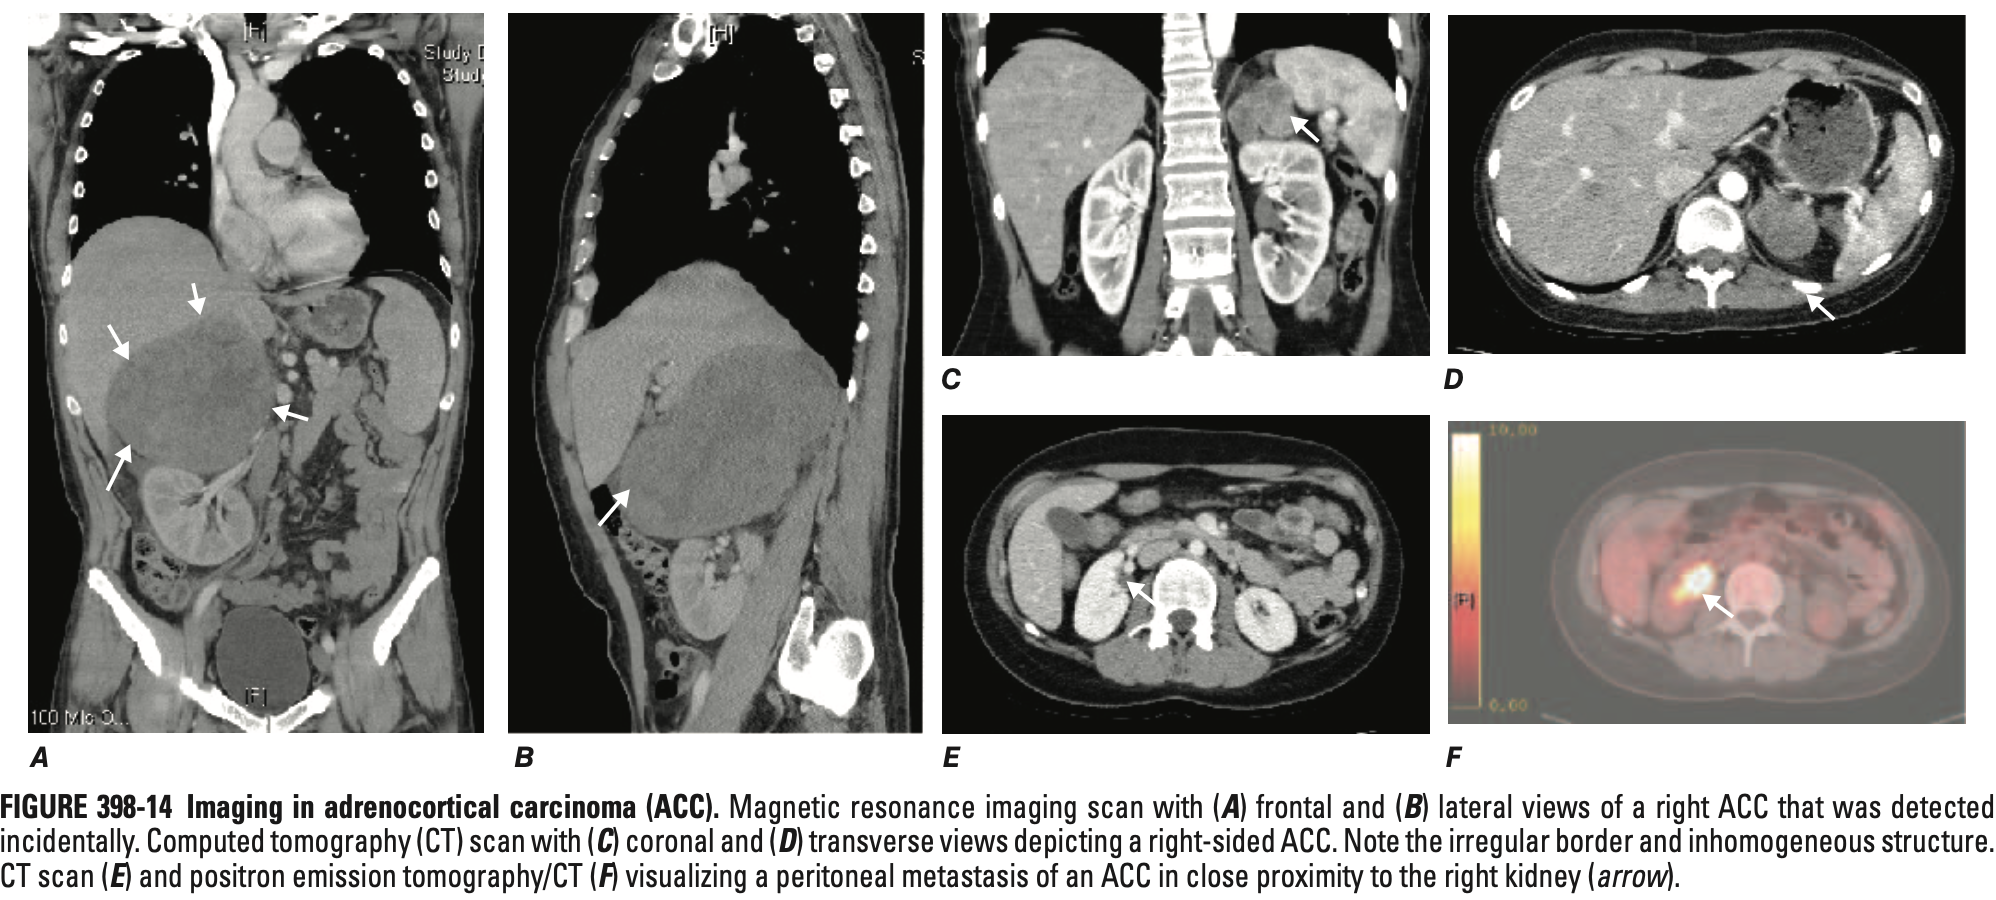

• CT 소견 (특징적):

• 크기 > 4cm (종양이 클수록 악성 가능성 급증)

• 불규칙한 경계 및 내부 괴사/출혈/석회화

• 높은 비조영 증강 밀도 (> 20 HU) 및 지연된 조영제 씻김(Washout) 현상

• MRI: 혈관 침범(하대정맥 등) 평가에 유용

• FDG-PET: 국소 재발이나 작은 전이를 찾는데 유용 (악성과 양성 종양 감별에는 사용 불가)